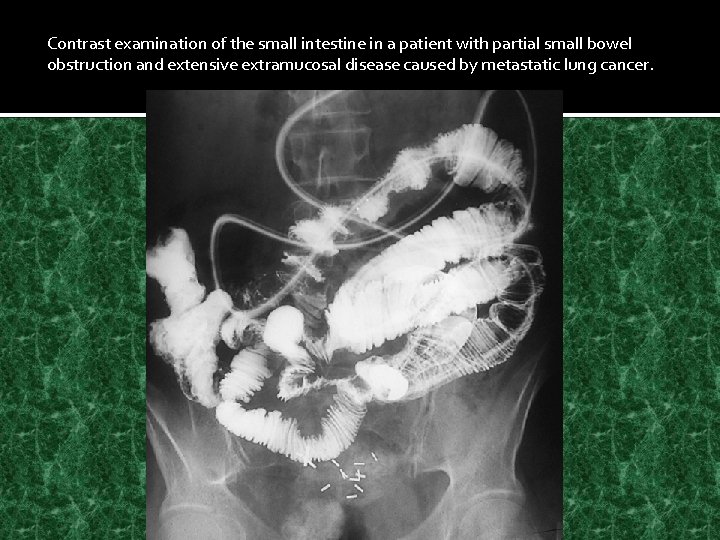

Contrast examination of the small intestine in a patient with partial small bowel obstruction and extensive extramucosal disease caused by metastatic lung cancer.